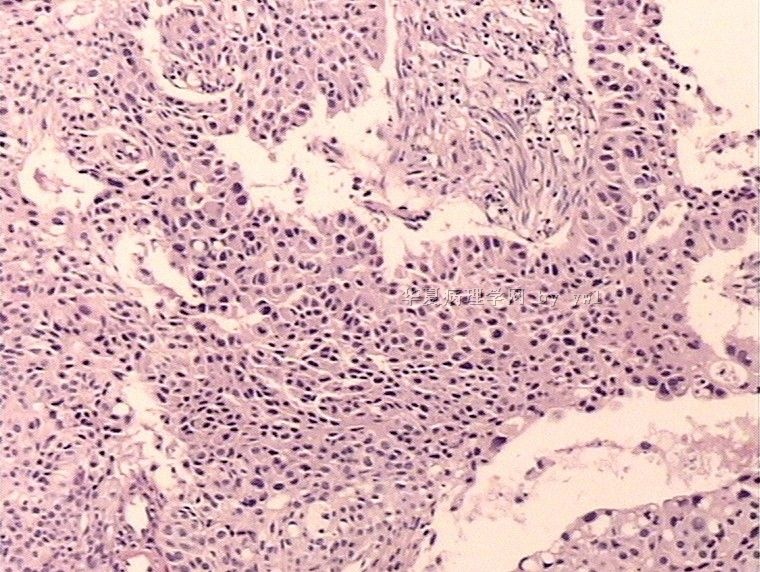

腺鳞癌?

姓    名: ××× 性别:   年龄:  39岁

标本名称:  宫颈活检

简要病史:  同房出血3次,tct HSIL

考虑:原位腺癌,小灶性区域有鳞状上皮向间质内浸润,考虑有鳞状细胞癌结构。

• 腺鳞癌?图2

图2